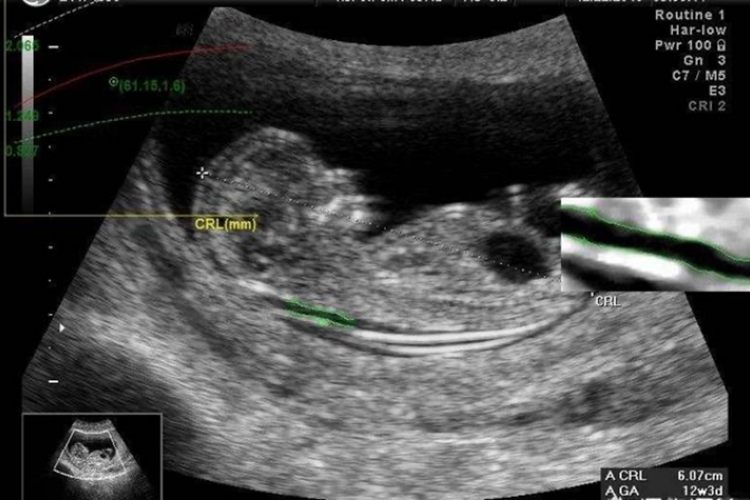

1、基础颈项透明层厚度测量检查检查:300-500元,基础检查专注于测量胎儿颈部皮下组织的液体积聚程度,以此评估染色体异常的风险。服务通常在孕早期,在11-14周进行,用来筛查唐氏综合征等遗传性疾病。费用相对较低,适用于广泛人群。

2、综合性产前筛查包:800-1500元,综合性筛查包结合了颈项透明层厚度测量检查检查与血清学筛查,通过检测母体血液中的特定生物标记物,进一步提高筛查准确率。这一层级的服务适合希望获取更全面风险评估的孕妇,特别是那些年龄较大、有遗传疾病家族史或前次妊娠有异常记录的群体。